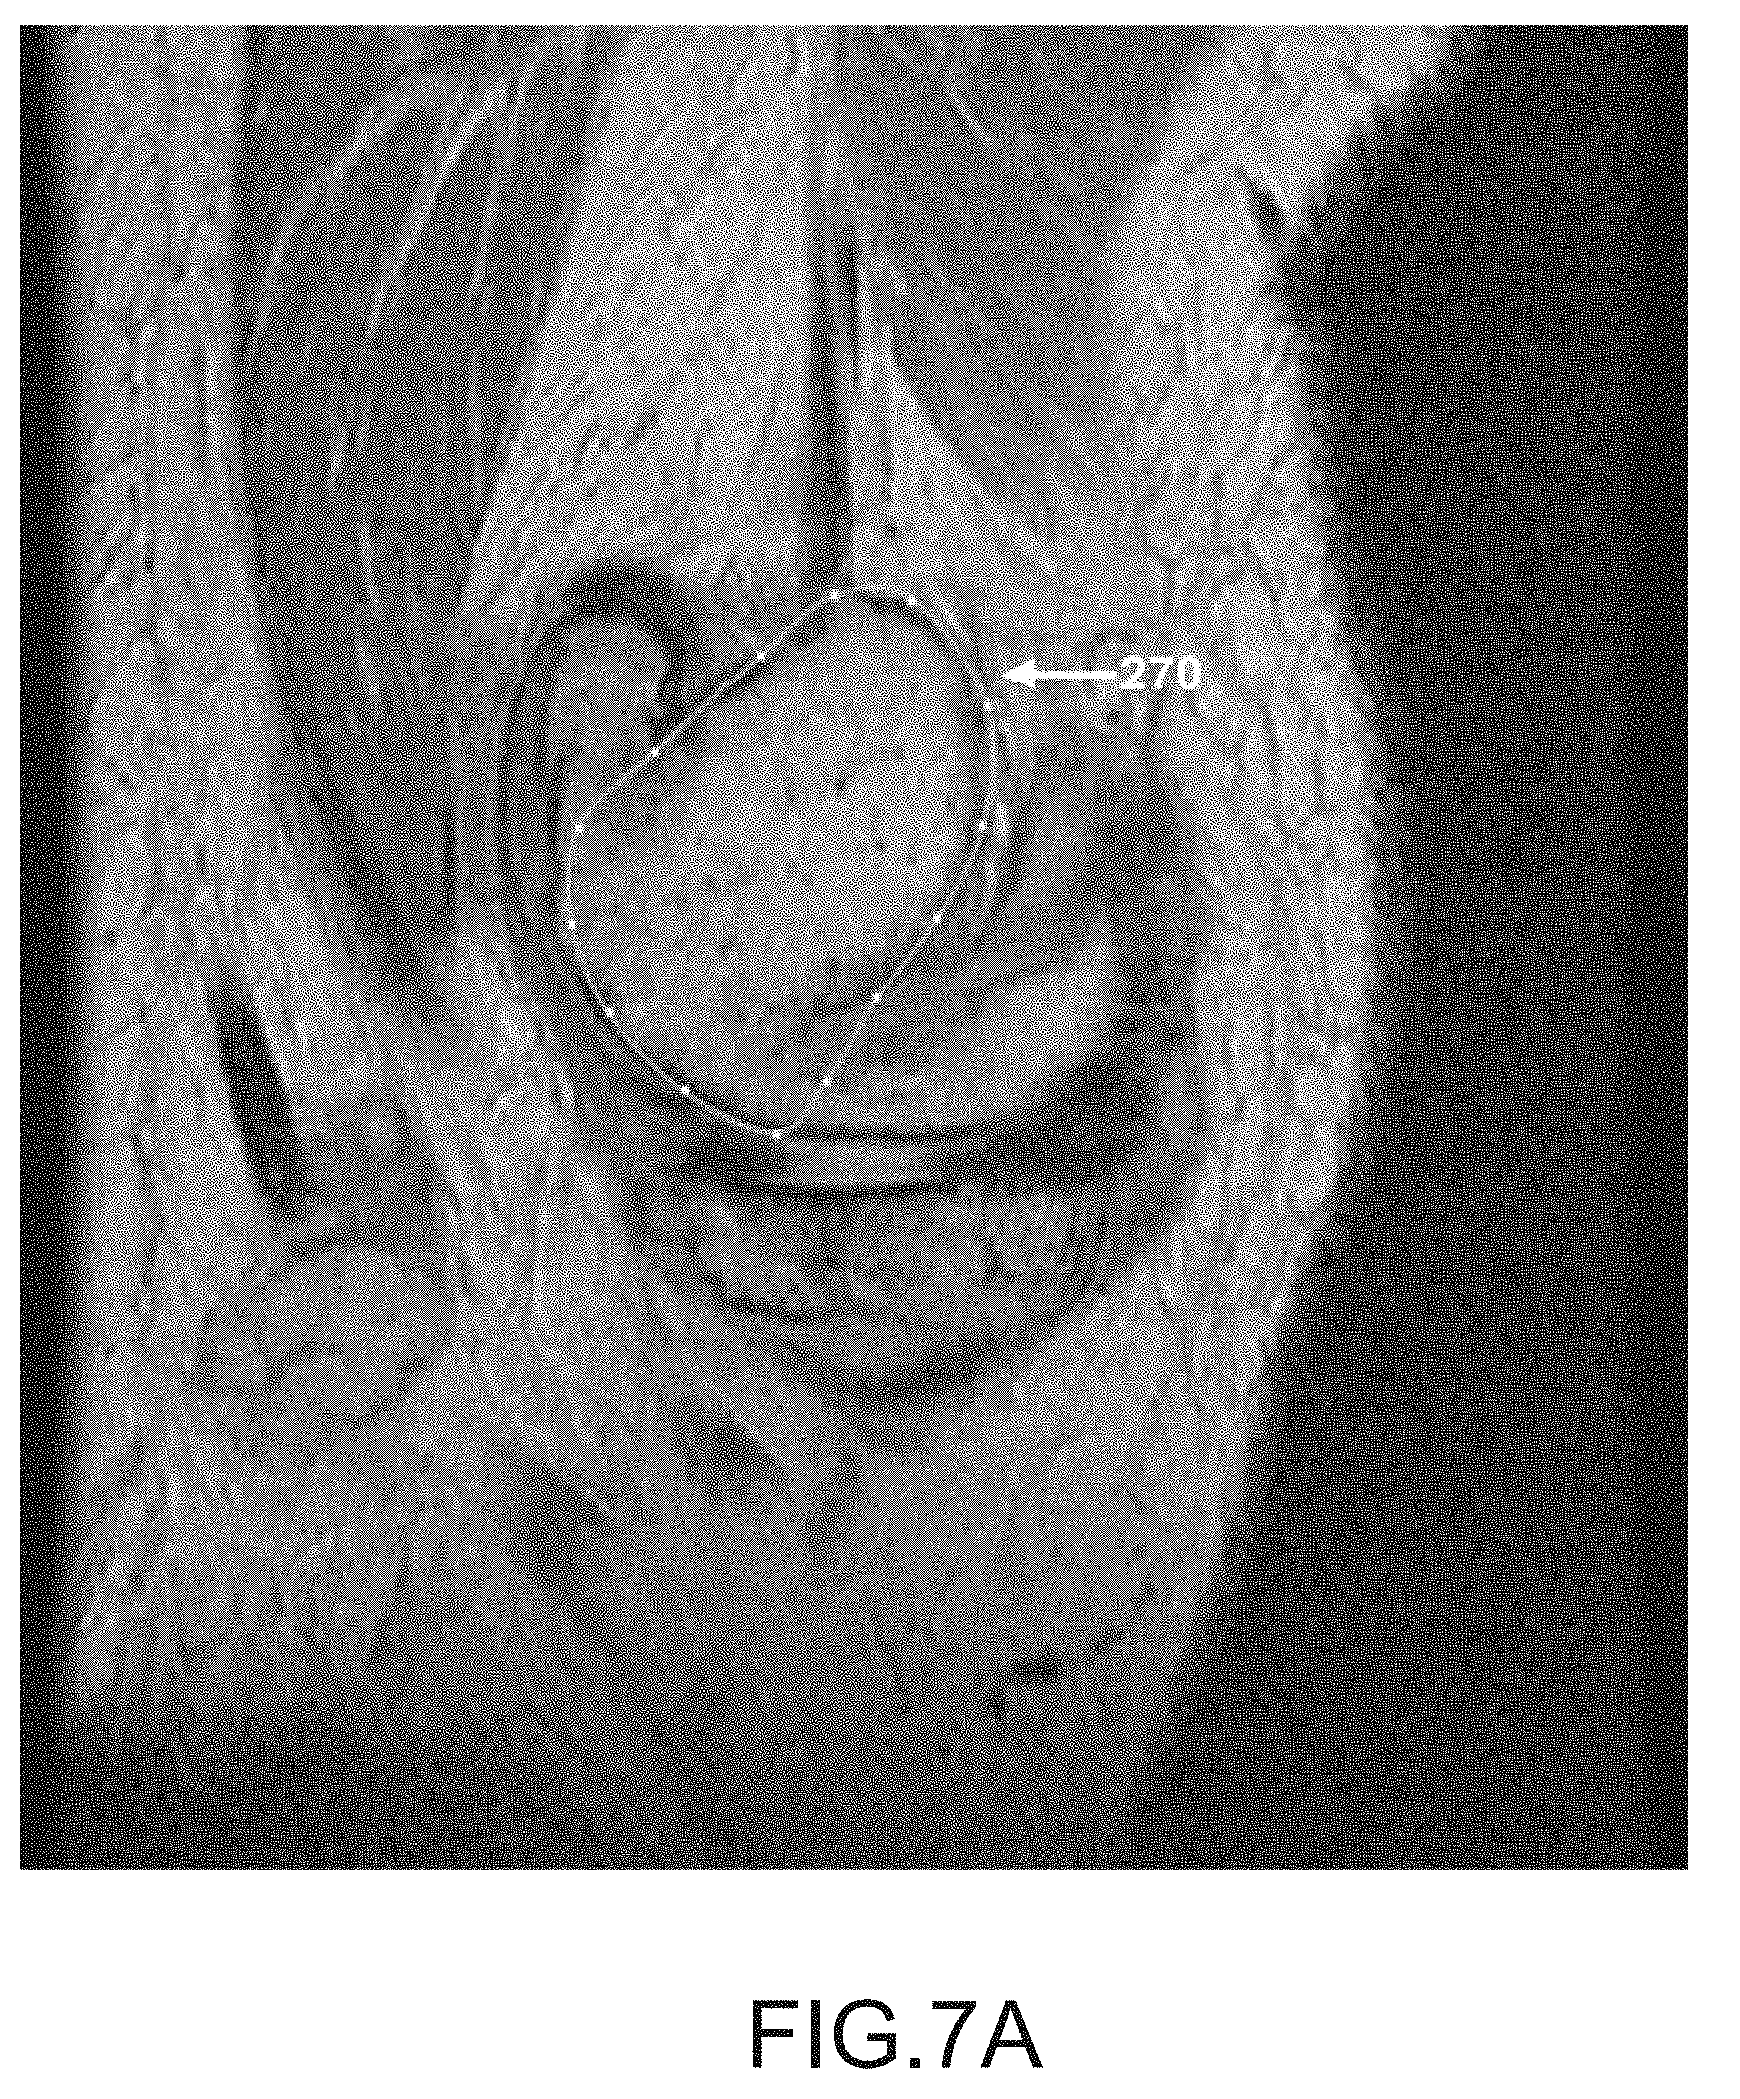

FIG. 7A is a sagittal plane image slice of a segmented femur.

[0051]

After operation 250 obtains scan data (e.g., scan images 16) generated by imager 8, operation 252 may be performed to segment the femur data of the scan data. During this operation, the femur may be located and spline curves 270 may be generated to outline the femur shape or contour lines in the scan slices, as depicted in FIGS. 7A-7K. It should be appreciated that one or more spline curves may be generated in each slice to outline the femur contour depending on the shape and curvature of the femur as well as the femur orientation relative to the slice direction.

[0163]